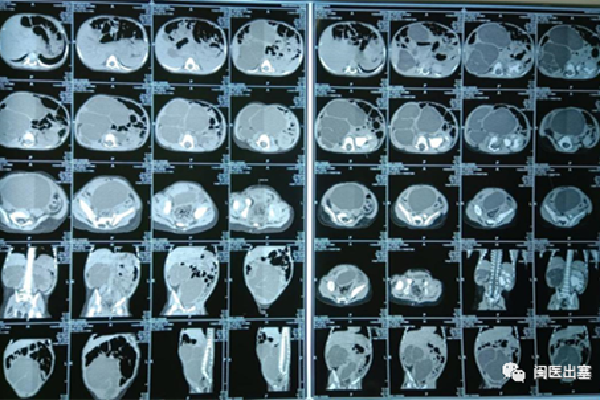

病例二:腹腔巨大的肿块“消失”了,患儿,14月,是一个早产儿,消瘦,发育也较同龄人慢,出生时双侧睾丸未下降到阴囊,考虑患儿很小,医生建议暂时先观察。随着患儿出现发烧,经过医生检查考虑肾多发囊肿继发感染,消炎治疗后症状改善,但仍有反复发作,腹部明显膨隆。查Ct增强发现腹腔巨大占位,右肾基本看不到正常结构。

经过评估后建议家属行腹腔探查,术中发现腹腔巨大囊性占位来源于右侧输尿管,而且发现右侧输尿管末端并未通向膀胱,而是个盲端,左肾及输尿管完整,双侧睾丸位于腹腔。考虑:右肾萎缩功能丧失,右侧输尿管先天发育异常伴巨大囊性变。顺着囊壁小心分离,完整切除右侧病变输尿管和肾脏、双侧睾丸固定下降。